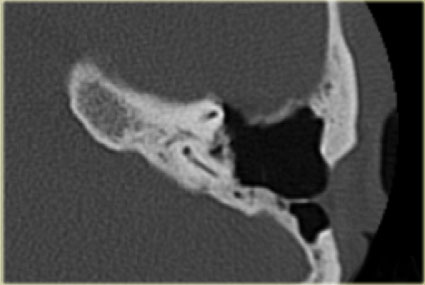

Bên trái là hình ảnh của một bé gái 2 tuổi.

Các hình ảnh từ kết quả chụp CT được thực hiện trước khi cấy ốc tai điện tử.

Quan sát thấy dị dạng nhẹ ở đỉnh ốc tai – không có sự phân tách giữa vòng thứ hai và vòng thứ ba, và trụ ốc tai xương vắng mặt.

Cống tiền đình bình thường.